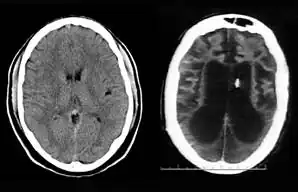

On August 10, 2001, on remand from the Florida Second District Court of Appeal, Judge Greer heard a motion from the Schindlers claiming that new medical treatment could restore sufficient cognitive ability such that Terri Schiavo herself would be able to decide to continue life-prolonging measures. The court also heard motions from the Schindlers to remove the guardian (Michael Schiavo) and to require Judge Greer to recuse himself. Judge Greer denied the motions and the Schindlers appealed to the Second District Court of Appeals. On October 17, 2001, the Court of Appeal affirmed the denials of the motions to remove and recuse. The Court of Appeals acknowledged that their opinion misled the trial court, and they remanded the question of Terri Schiavo's wishes back to the trial court and required an evidentiary hearing to be held. The court specified that five board certified neurologists were to testify. The Schindlers were allowed to choose two doctors to present findings at an evidentiary hearing while Schiavo could introduce two rebuttal experts. Finally, the trial court itself would appoint a new independent physician to examine and evaluate Terri Schiavo's condition. These decisions, all published in a single order by the Florida Second District Court of Appeal,[37] came to be known by the court as Schiavo III in its later rulings. In October 2002, on remand by the Second District Court of Appeal, an evidentiary hearing was held in Judge Greer's court to determine whether new therapy treatments could help Terri Schiavo restore any cognitive function. In preparation for the trial, a new computed axial tomography scan (CAT scan) was performed, which showed severe cerebral atrophy. An EEG showed no measurable brain activity. The five physicians chosen were William Maxfield, a radiologist, and four neurologists: William Hammesfahr, Ronald Cranford, Melvin Greer and Peter Bambakidis.[38]

The five doctors examined Terri Schiavo's medical records, brain scans, the videos, and Terri herself. Cranford, Greer, and Bambakidis testified that Terri Schiavo was in a persistent vegetative state (PVS). Maxfield and Hammesfahr testified that she was in a minimally conscious state. As part of the court-ordered medical exam, six hours of video of Terri Schiavo were taped and filed at the Pinellas County courthouse. The tape included Terri Schiavo with her mother and neurologist William Hammesfahr. The entire tape was viewed by Judge Greer, who wrote, Terri "clearly does not consistently respond to her mother". From that six hours of video, the Schindlers and their supporters produced six video clips intended to support their case, totaling less than six minutes, and released those clips to public websites.[1] Judge Greer ruled that Terri Schiavo was in a PVS, and was beyond hope of significant improvement. The trial court order was particularly critical of Hammesfahr's testimony, which claimed positive results in similar cases by use of vasodilation therapy, the success of which is unsupported in the medical literature.[39] This ruling was later affirmed by Florida's Second District Court of Appeal, which stated that "this court has closely examined all of the evidence in the record", and "we have ... carefully observed the video tapes in their entirety." The court concluded that "if we were called upon to review the guardianship court's decision de novo, we would still affirm it." This decision by the Second District Court of Appeals[40] came to be known as Schiavo IV in later rulings.

Schiavo's body was taken to the Office of the District 6 Medical Examiner for Pinellas and Pasco counties, based in Largo, Florida. The autopsy was conducted on April 1, 2005, and revealed extensive brain damage. The manner of death was certified as "undetermined." The autopsy was led by Chief Medical Examiner Jon R. Thogmartin. In addition to consultation with a neuropathologist (Stephen J. Nelson), Thogmartin also arranged for specialized cardiac and genetic examinations to be made. The official autopsy report[32] was released on June 15, 2005. In addition to studying Terri Schiavo's remains, Thogmartin scoured court, medical and other records and interviewed her family members, doctors and other relevant parties. Examination of Schiavo's nervous system, by neuropathologist Stephen J. Nelson, revealed extensive injury. The brain itself weighed only 615 g (21.7 oz), only half the weight expected for a female of her age, height, and weight, due to the loss of a massive number of neurons. Microscopic examination revealed extensive damage to nearly all brain regions, including the cerebral cortex, the thalamus, the basal ganglia, the hippocampus, the cerebellum, and the midbrain. The neuropathologic changes in her brain were precisely of the type seen in patients who enter a PVS following cardiac arrest. Throughout the cerebral cortex, the large pyramidal neurons that comprise some 70% of cortical cells – critical to the functioning of the cortex – were completely lost. The pattern of damage to the cortex, with injury tending to worsen from the front of the cortex to the back, was also typical. There was marked damage to important relay circuits deep in the brain (the thalamus) – another common pathologic finding in cases of PVS. The damage was, in the words of Thogmartin, "irreversible, and no amount of therapy or treatment would have regenerated the massive loss of neurons."[70]